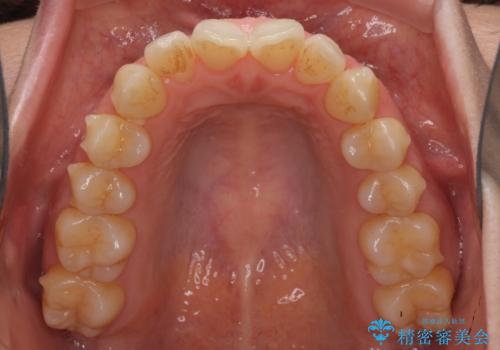

前歯の叢生とオープンバイト インビザラインでの矯正治療

- 前歯の開咬を気にして来院された患者様です。

開咬の治療は、前歯を閉じるように動かすとともに、上下臼歯を圧下(骨内にめり込ませる)させることで進めて行きます。

インビザラインは臼歯の圧下を効果的に行えるため、インビザラインを用いて矯正治療を行うこととしました。